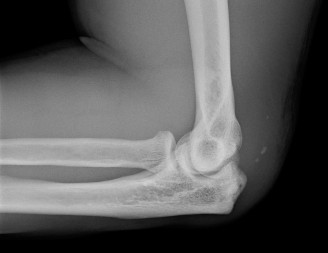

The correct answer is (C). Although pectoralis major muscle (PMM) injuries are

primarily diagnosed clinically, MRI is the imaging modality of choice to evaluate a PMM tendon injury. The extent and location of the injury can many times be assessed with MRI. The Tietjen’s classification system can be used for PMM injuries. Type I is a contusion or sprain. Type II is a partial tear. Type III injuries are complete tears and further classified by anatomic location: III-A (muscle origin), III-B (muscle belly), III-C (musculotendinous junction), III-D (tendinous insertion). Further subclassification were suggested including III-E (bony avulsion from the insertion) and II-F (muscle tendon substance rupture). Type II and Type III injuries have been reported at rates of 9% and 91%, respectively. Among complete tears, type III-D has been reported as the most common (65%). Ultrasound is a reasonable alternative to MRI, particularly if its use means avoiding delay of surgical repair. Ultrasound is much more user-dependent. CT will not allow adequate soft tissue evaluation. Further radiographic evaluation is incorrect because a radiograph of the injured shoulder has already been obtained. The radiographic findings are often normal, but the clinician should look for bony avulsions. The characteristic findings on radiographs are soft tissue swelling and absence of the PMM shadow.

After evaluating the MRI, the patient is diagnosed with a complete rupture of the pectoralis major tendon (Fig. 2–79). What is the recommended first step in management?

Figure 2–79